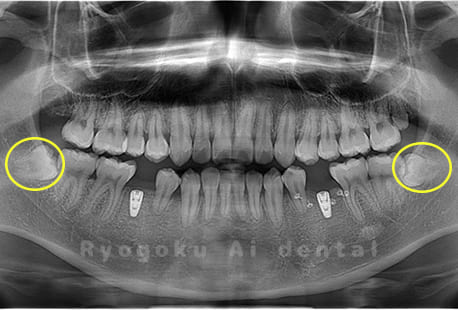

Case01

- 原因

- 水平埋伏智歯

- 治療内容

- 下顎の水平埋伏智歯を抜歯

<リスク・副作用>

手術後は痛み、腫れ、痺れなどの副作用が生じる場合があります。